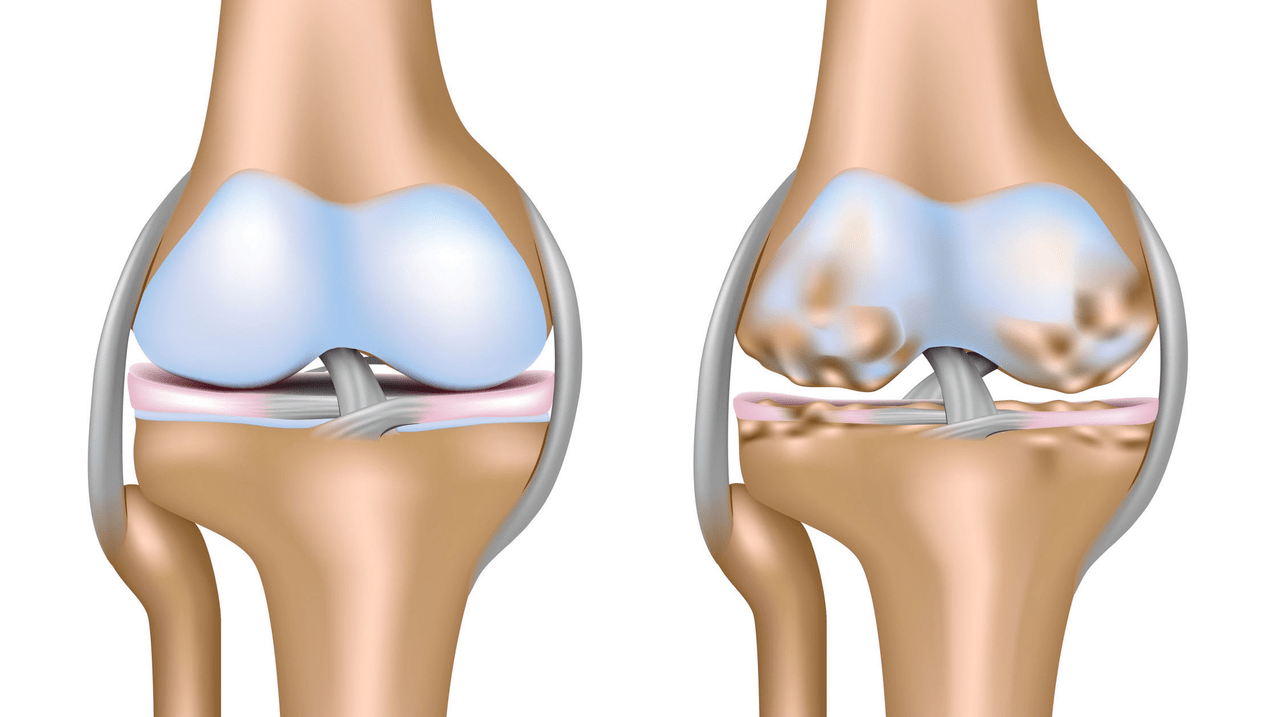

Arthrosis of the knee joint (gonarthrosis)is a progressive chronic disease of the knee joints with damage, thinning and destruction of its cartilaginous part (articular surfaces of the femur and tibia), as well as damage to the subchondral bone.Studies (arthroscopy and magnetic resonance imaging) have proven that in addition to damage to the articular cartilage, the menisci and synovial membrane also participate in the process.Gonarthrosis is one of the most common orthopedic pathologies.There are its synonyms - osteoarthritis (OA), deforming arthrosis.The disease is an important socio-economic problem, because it is widespread and significantly worsens the quality of life of patients due to constant pain, and it also becomes a cause of high disability.

Until the mid-eighties of the last century, there was no single definition of the disease.It was not until 1995 that the osteoarthritis committee of the American College of Rheumatology characterized the disease as the result of mechanical and biological factors that lead to an imbalance between the processes of degradation and synthesis of the extracellular matrix of articular cartilage.As a result, there is disintegration and degeneration of fibers, cracks, osteosclerosis and compaction of the cortical layer of subchondral bone are formed, osteophytes grow and subchondral cysts are formed.

In arthrosis (osteoarthrosis), in addition to the progressive destruction of cartilage, loss of its elasticity and cushioning properties, the bones are gradually involved in the process.Under load, sharp edges (exostoses) appear, which are mistaken for "salt deposits" - in classic arthrosis, salt deposition does not occur.As osteoarthritis progresses, it continues to "eat" the cartilage.Then the bone deforms, cysts form, all joint structures are affected, and the leg bends.

The first stage of the disease is characterized by primary changes in the hyaline cartilage.Bone structures are not affected.Blood supply in intraosseous vessels and capillaries is disturbed.The cartilage surface becomes dry and loses its smoothness.If the disease is accompanied by constant tense synovitis, then Baker's cyst (hernial protrusion of the joint capsule of the popliteal region) develops.After significant stress on the joint, a dull pain occurs.Slight swelling may occur, which disappears after rest.No deformation.

Gonarthrosis, II stage

In the second stage, the layer of cartilage becomes suddenly thinner, and in some places it is completely absent.Osteophytes appear along the edges of the joint surfaces.The qualitative and quantitative characteristics of the synovial fluid of the joint change - it becomes thicker, more viscous, which leads to the deterioration of its nutritional and lubricating properties.The pain is longer and more intense, and there is often a creaking sound when moving.There is mild or moderate limitation of motion and mild joint deformity.Taking analgesics helps relieve pain.

Gonarthrosis, stage III

Lack of cartilage in most affected areas, severe sclerosis (hardening) of the bones, many osteophytes and sharp narrowing or absence of the joint space.The pain is almost constant, the gait is disturbed.Mobility is severely limited, and joint deformations are noticeable.NSAIDs, physiotherapy and other standard methods of treatment for knee arthrosis are ineffective.